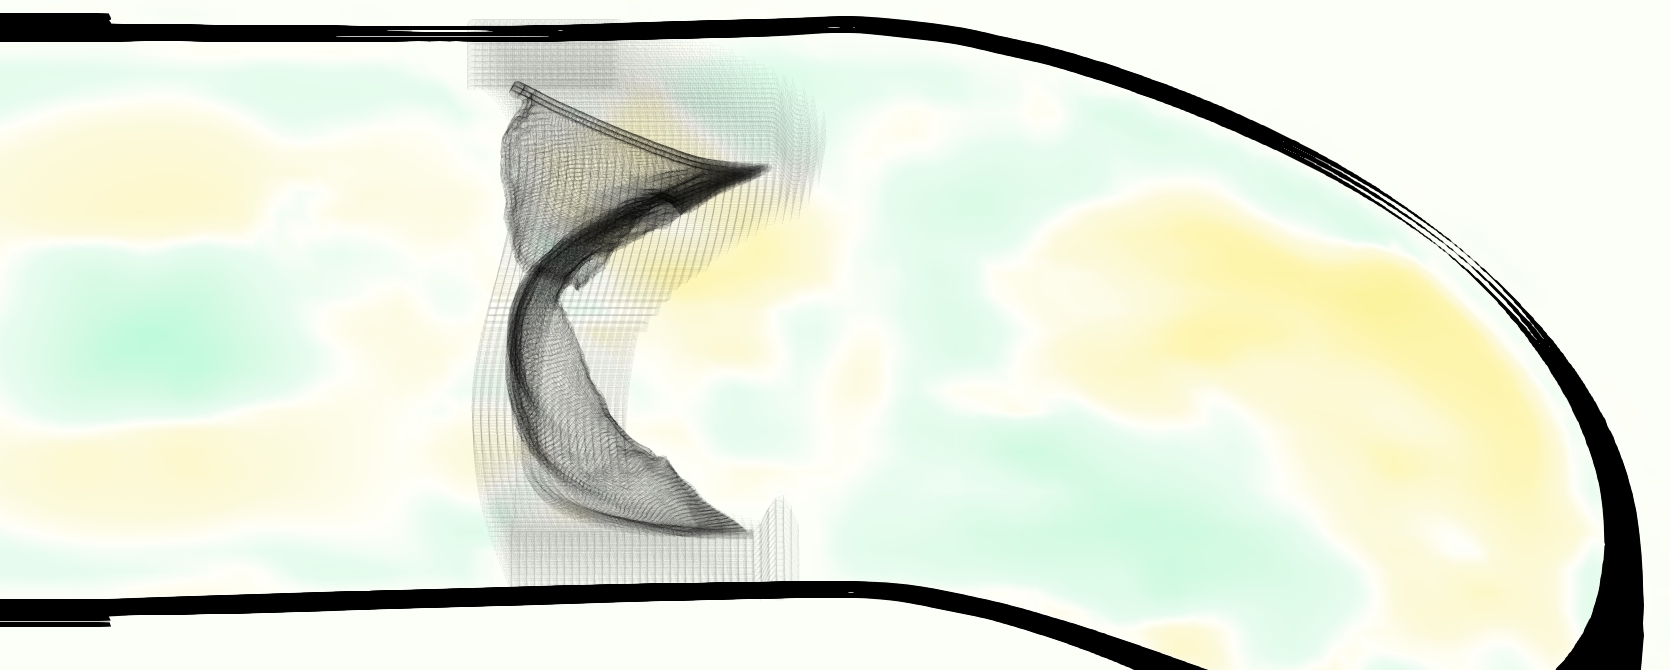

Slice views of the (axial) component of fluid velocity in the axial plane, orthogonal to the flow direction, show that the simulation replicated the development of the jet over the cardiac cycle. At each phase, the simulation matched the forward speed of the core of the jet and the locations of reverse flow back towards the valve annulus. While there are some differences in the shape of the jet at certain phases and locations, the simulation clearly produced the general dynamics of the cardiac cycle that are seen in the experiment.

At = 0, the axial slice directly at the valve annulus shown in columns 1 and 2 in Figure 6, there was excellent agreement between the simulation and experiment over the cardiac cycle in the speed and shape of the jet through the valve. In both cases, the axial velocity increased as the flow accelerated during systole and the valve leaflets opened, then decreased during diastole with slight negative velocity before the valve leaflets were fully closed. The forward flow through the valve annulus did not form a full circle, but rather developed a triangular shape with a point of the triangle forming along the interior curve of the vessel, at the bottom of the axial slices. At = 0, the points of this triangular jet shape aligned with the commissures of the valve. This shape persisted during peak systole and was well-matched by the simulation.

The axial slice = 0.625 cm, shown in columns 3 and 4 in Figure 6, cut through the support scaffolding of the valve and the leaflets when they are open. In the experimental data, the shape of the jet changed as it moved downstream. A triangular shape occurred, but the points were then aligned with the middle of each open leaflet as opposed to the commissures. Those points were also more rounded than they were at = 0. The peak velocity of the jet was faster at = 0.625 cm than at = 0, as the flow accelerated through the open valve leaflets. The simulation produced these features at = 0.625 cm. The triangular shape of the jet shifted similarly, and its speed increased compared to the upstream slice. As the flow decelerated into diastole, the jet shape remained roughly triangular but diminished in intensity before disappearing after valve closure.

The jet continued to develop at = 1.25 cm, an axial slice immediately downstream of the valve scaffolding and open leaflets, shown in columns 5 and 6 in Figure 6. In the experimental data, the points of the triangular jet shape extended further towards the vessel wall. In addition, regions of reversed flow developed in the locations downstream of the commissures, resulting in curved sides to the shape of the jet. Each tip of the jet was unique, due to variations in the individual leaflets in the physical bioprosthetic valve. These variations are apparent in the velocity fields, possibly because the jet edges are similar enough cycle to cycle that irregularities are still being captured even with phase averaging. Further discussion of these features can be found in Schiavone et al. [39], which showed that the jet tip shapes occurred in different pulmonary anatomies, demonstrating that they were likely due to inherent properties of each leaflet. The leaflets in the mathematical model of the valve are identical, so these nuances in leaflet variation could not be replicated. The simulation did capture some of the extension of the tips of the jet, as they were closer to vessel wall at slice = 1.25 cm than = 0.625 cm. The curves in the triangular sides of the jet were also present in the simulation, though they were less pronounced than the experimental data. At both = 0.625 cm and = 1.25 cm, the jet shape in the simulation was smoother than the jet in experiment. It is possible that the free edges of the leaflets in the mathematical model are not fully replicating the behavior of the physical leaflets of the bioprosthetic valve, in particular the amplitude or frequency of leaflet flutter, leading to the variations seen in the jet shape at = 1.25 cm downstream of the leaflet edges. The simulation, however, does capture the key features of the triangular shape and speed of the jet. Overall, qualitative comparisons demonstrated that the simulation reproduced key features of the flow during systole and diastole.